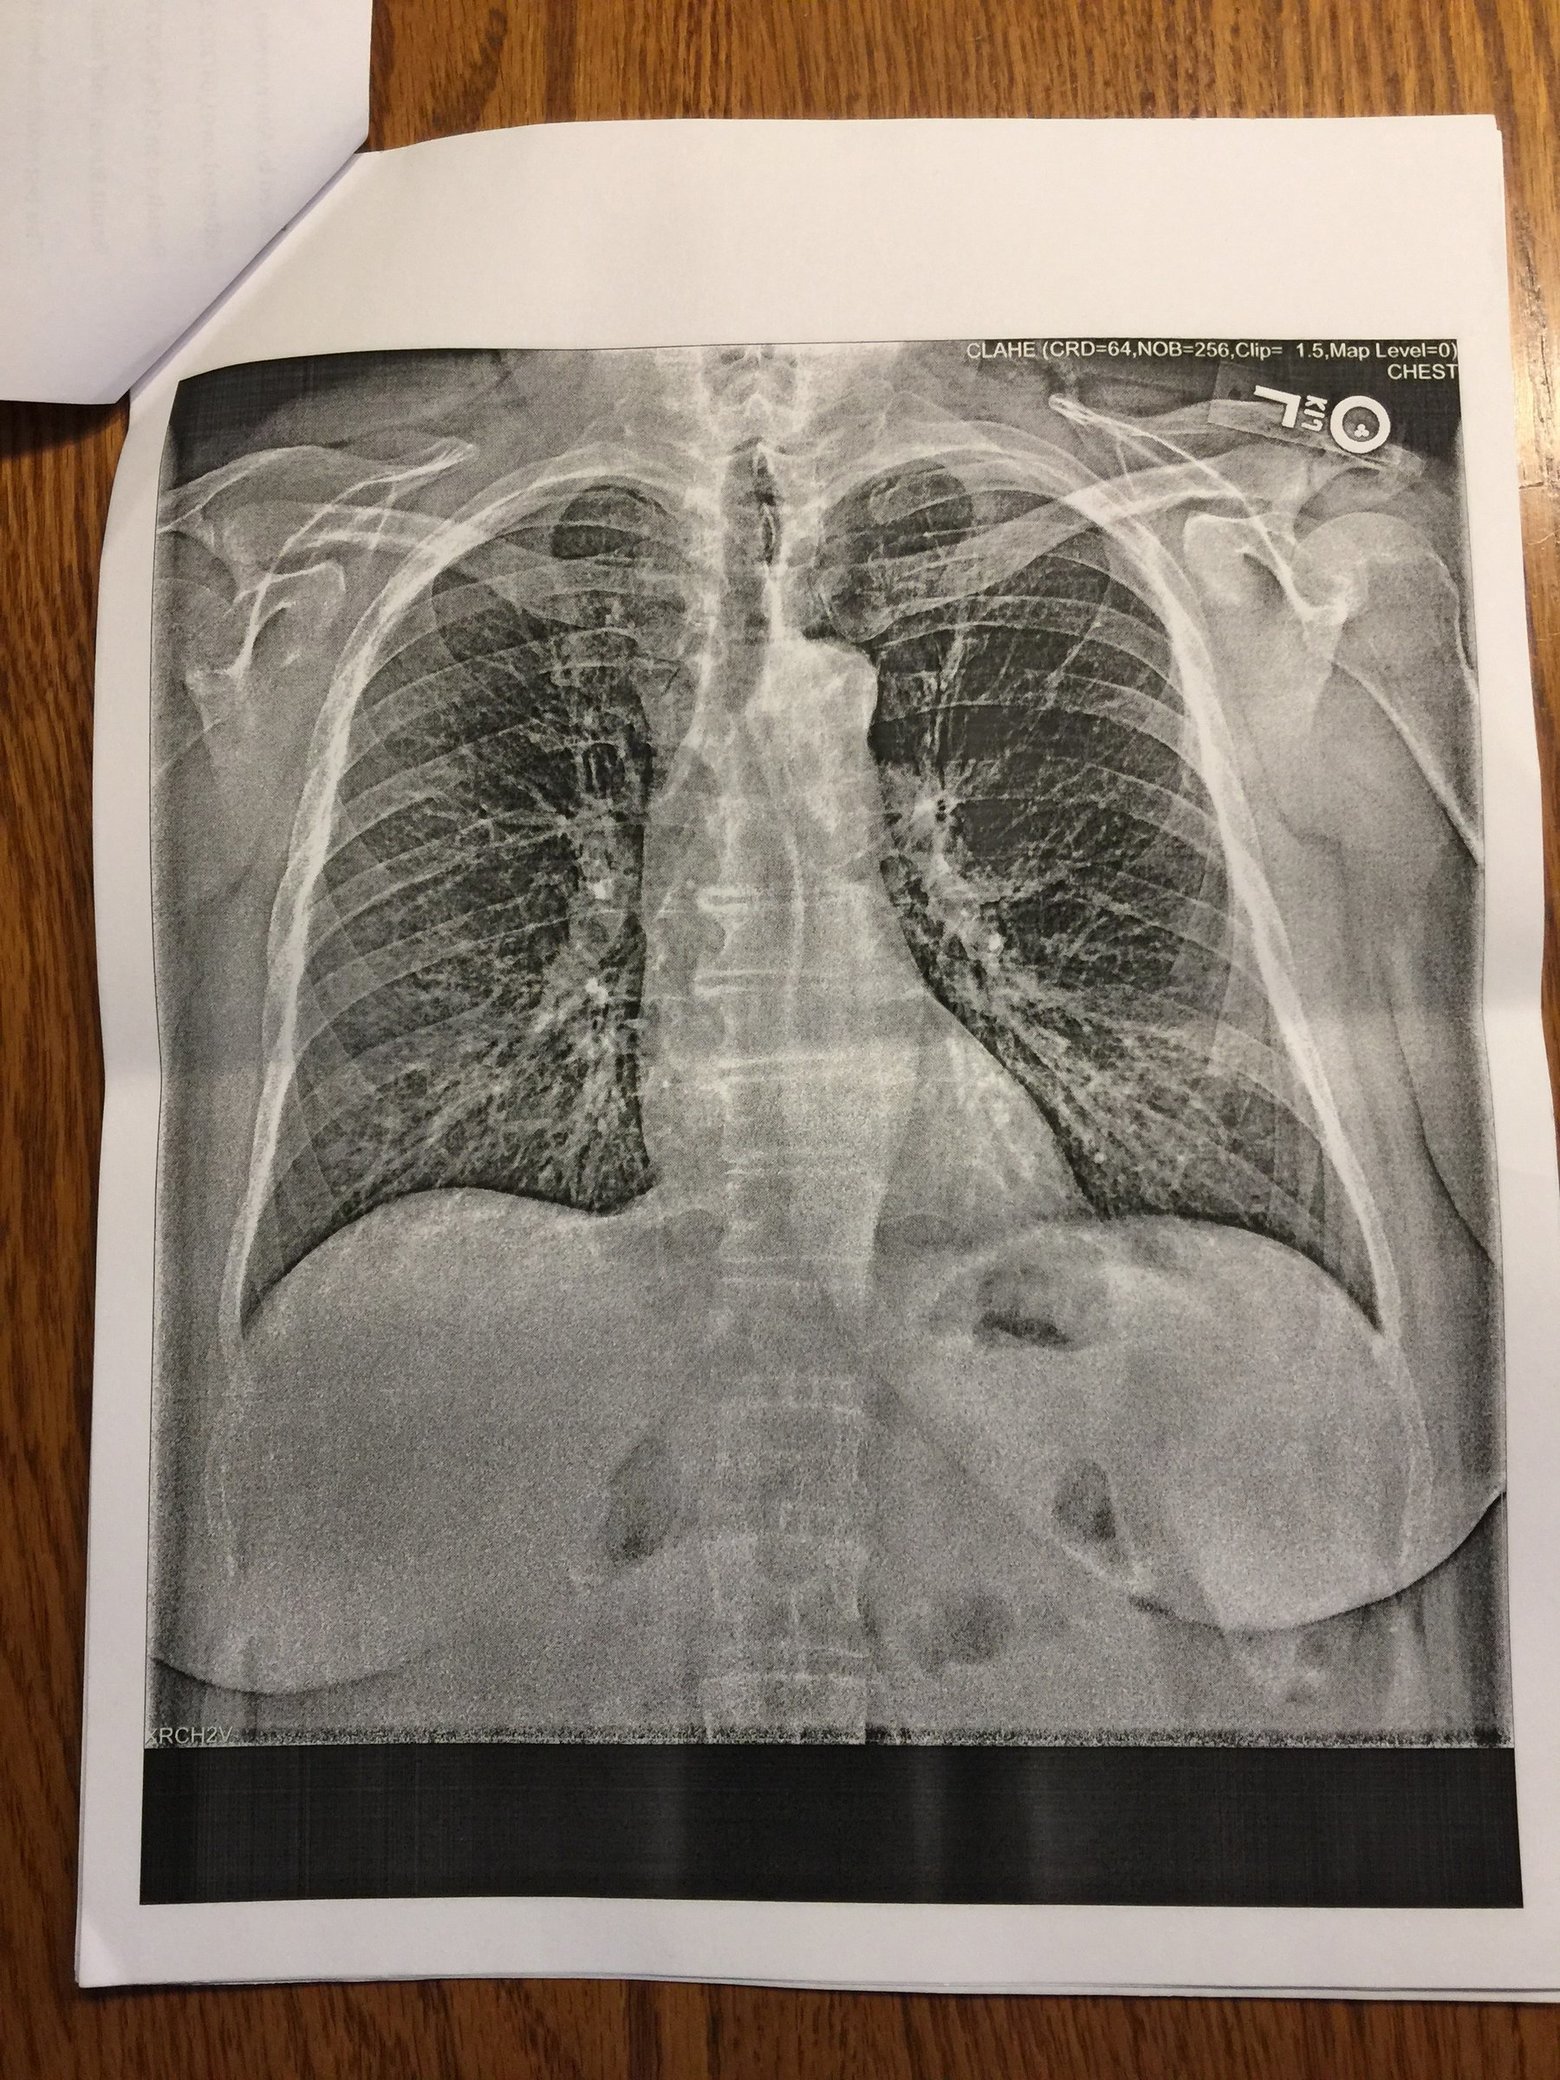

華盛頓州患者在1月的肺部X光片,這名患者後檢測抗體呈陽性